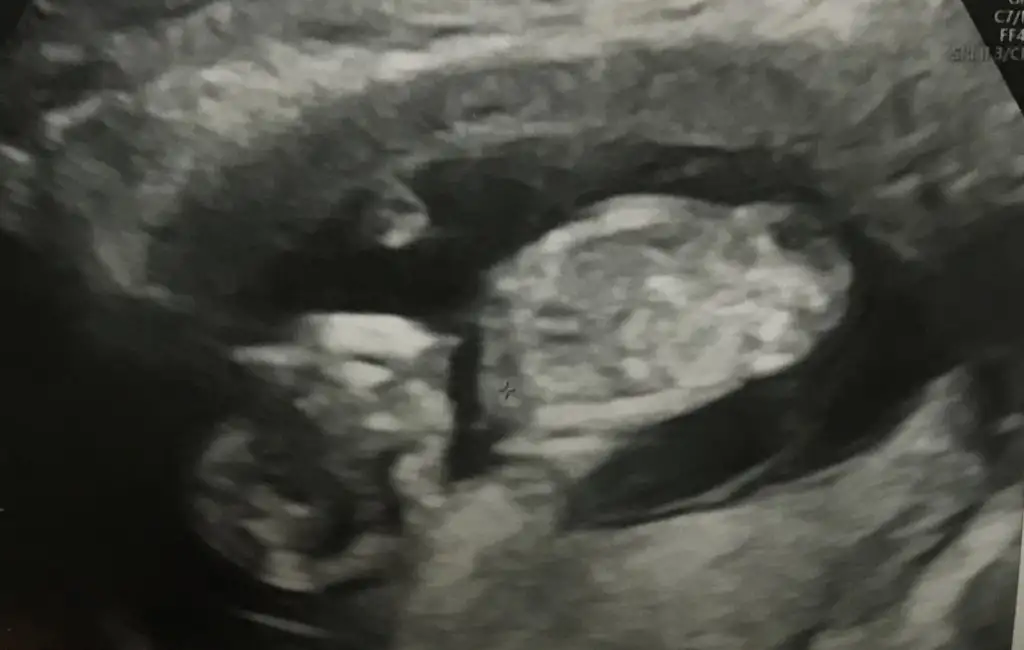

Ne demiştim önce bilmiyorum ama kız diyorumCanımm daha öncede konusmustık seninle 12-13 haftalarda tekrar atmaamı istemiştintekrar bakabilir misin

Öncede kız demiştin canım çok teşekkür ederimNe demiştim önce bilmiyorum ama kız diyorum